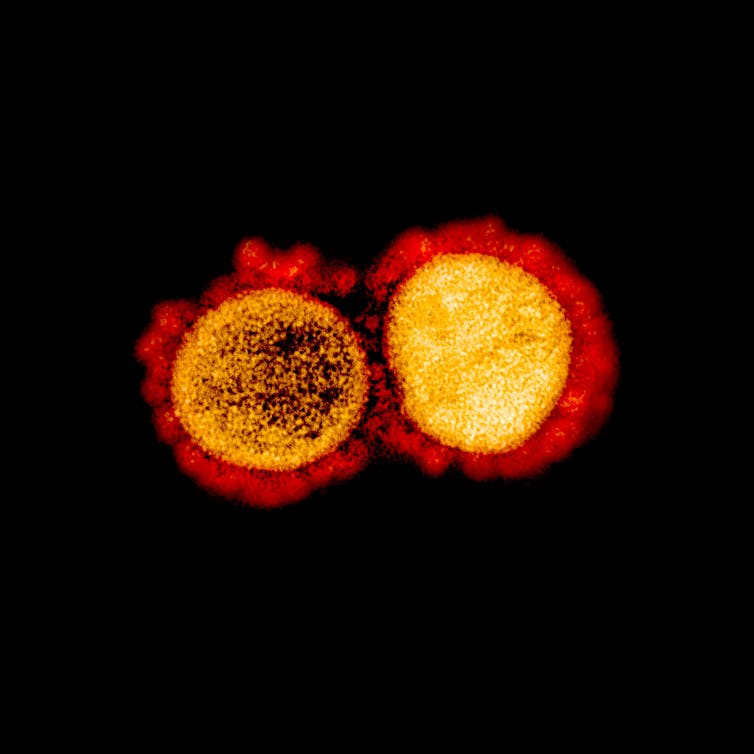

En los libros de texto los virus son seres inertes. No cumplen los criterios que definen a un ser vivo. El coronavirus, entre ellos, no es un organismo celular, con metabolismo, crecimiento y desarrollo, homeostasis, respuesta a estímulos y al medio. Solo cumple dos características básicas en la definición: evoluciona y se reproduce, aunque, al no tener ribosomas propios, necesita la maquinaria del hospedador celular, por ejemplo un ser humano, para reproducirse.

Desde la descripción del primer virus del tabaco por el científico Dmitri Ivanovsky en 1892, se han descrito más de 9 000 especies de virus en detalle, aunque se estima que hay millones de tipos en el ambiente. Y todos son extremadamente simples. Están formados por material genético (ARN o ADN), una cápsida proteica y, en algunos casos, también una cubierta de lípidos.

Los virus, como vemos que ocurre con el coronavirus, están sujetos a evolución y a selección natural de manera extraordinariamente parecida a cualquier otro ser vivo. Los virus (huéspedes) y las células (hospedadores) coevolucionan como fruto de su relación antagonista.